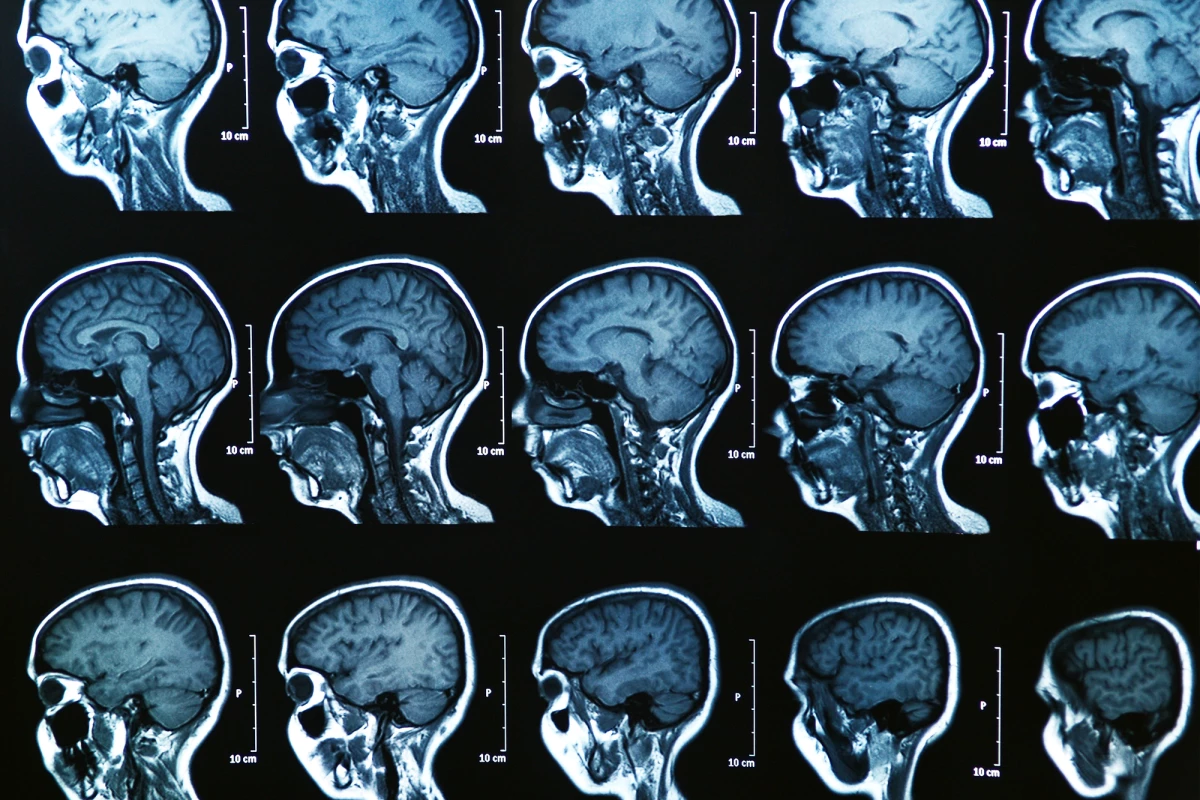

MRI brain scans of MS patients, based on the newly identified subtypes

The team set an AI tool called Subtype and Stage Inference (SuStaIn) to work on the MRI brain scans of 6,322 MS patients. In doing so, it identified three new subtypes of MS, which the scientists later named “cortex-led,” “normal-appearing white matter-led,” and “lesion-led.” These names are based on where and what type of abnormalities appear earliest.